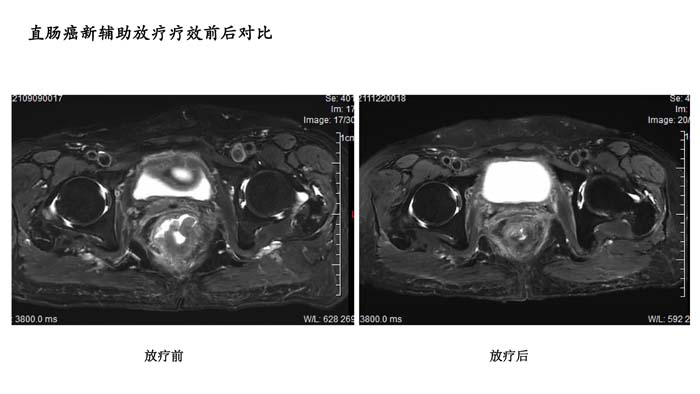

直肠癌新辅助放疗疗效前后对比1

- 直肠癌新辅助放疗疗效前后对比1